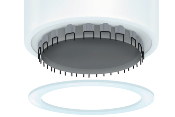

zsr 2.0 δευτερησ γενιασ

Μοναδικά Χαρακτηριστικά

Μεγάλο Παράθυρο

Για τη σωστή τοποθέτηση της συσκευής

Αιμοστατικός δακτύλιος σιλικόνης

Για αιμόσταση, προστασία και ταχεία επούλωση του τραύματος

Ειδική εγκοπή

Για την προστασία του χαλινού